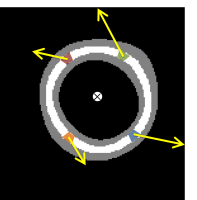

In a LV model of the shape of a perfect hollow truncated ellipsoid, the region of integration (ROI) is defined as a subregion of the LV of similar shape and smaller width aligned with the LV short axis. The cross sections of this region with the slice planes are rings of various radii and constant width. It is important that the ROI is equi-width and equidistant from the LV endocardial and epicardial surfaces in order that the error in integration is minimum. To take into consideration variations of the real LV shape from this LV shape model, the ROI is adjusted to another equiwidth and equidistant region sitting in the LV wall. This region is formed by closed straps around the medial axis of the LV cross sections on each slice, which are extended along the longitudinal direction. The closed straps (also called rings in this work), are computed as the dilated skeleton of the myocardial mask on each slice.

In case of model B symmetry, it is also proved that . Let (in blue, Fig.1c), (in green, Fig.1c, (in red, Fig.1c) and (in orange, Fig.1c) be four infinitesimal segments of with and located symmetrically in pairs about the bisector line as defined in model B, and located symmetrically in pairs about the centre. As above . If are the corresponding velocities at and since model B symmetry applies, the following relationships for the velocity magnitudes and velocity directions occur. For this, the sum , hence as above . By integration over the entire it is proved that and thus .